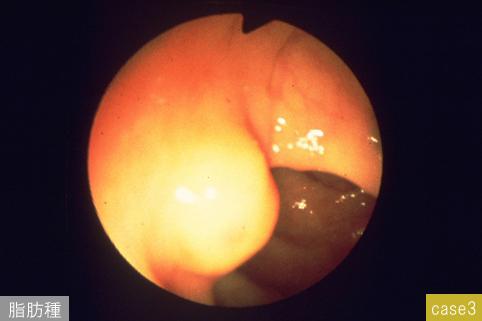

Various benign submucosal tumors and submucosal-tumor like lesions.

others/

Large intestine(Colon)/Transverse colon

Endoscopy

10 - 14